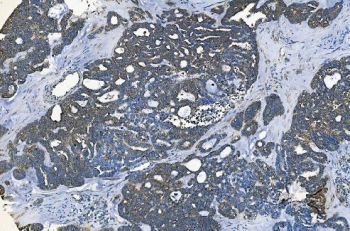

IHC staining of FFPE human ovarian cancer with GABARAP antibody. HIER: boil tissue sections in pH8 EDTA for 20 min and allow to cool before testing.